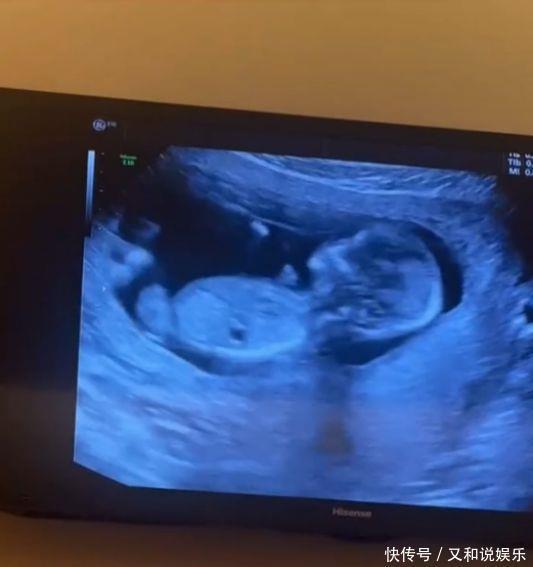

“刘能”王小利次子官宣当爸,才结婚两个月,幸福公开老婆孕肚照